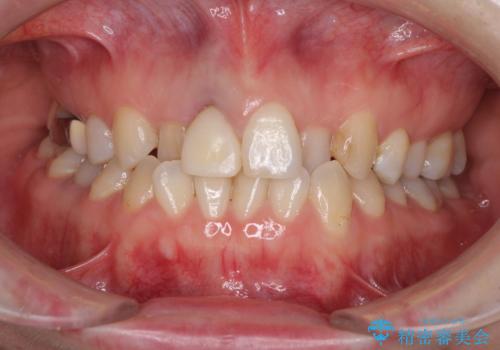

前歯の反対咬合をワイヤー矯正で改善して噛みやすく